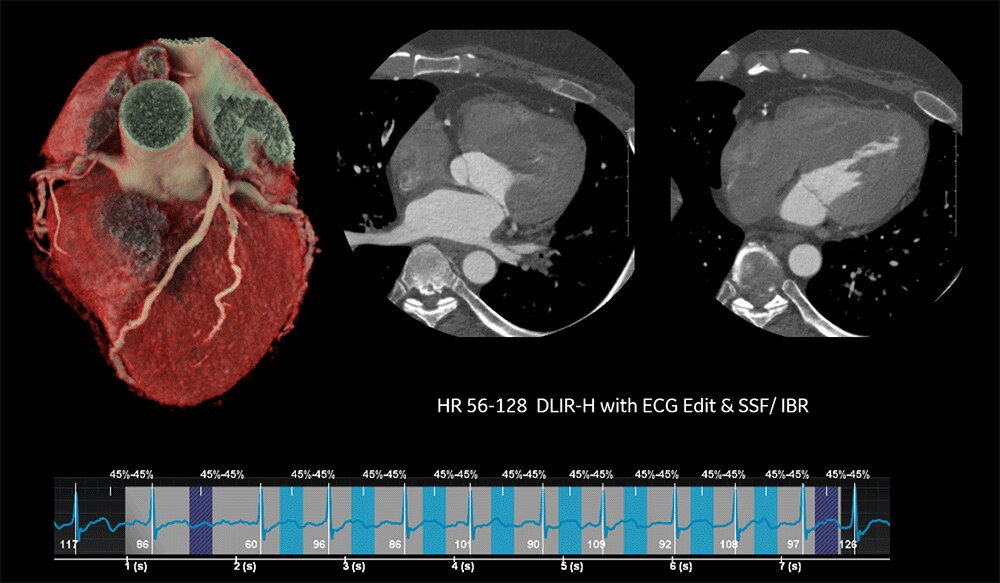

Revolution Ascendで撮影した画像はSnapShot Freeze(冠動脈モーションアーチファクト低減機能)を使用することが可能であり、4cmカバレッジCTでありながら高心拍ならびに不整脈に対応した心臓撮影が可能である。ここではその1例となる画像を紹介する。

HR56-128の症例においても、GECTのCardiac Technologyである、SnapShot Freeze, ECG Editor, IBR (バンディングアーチファクト低減機能)を使用することで、短時間で画像処理が可能である。